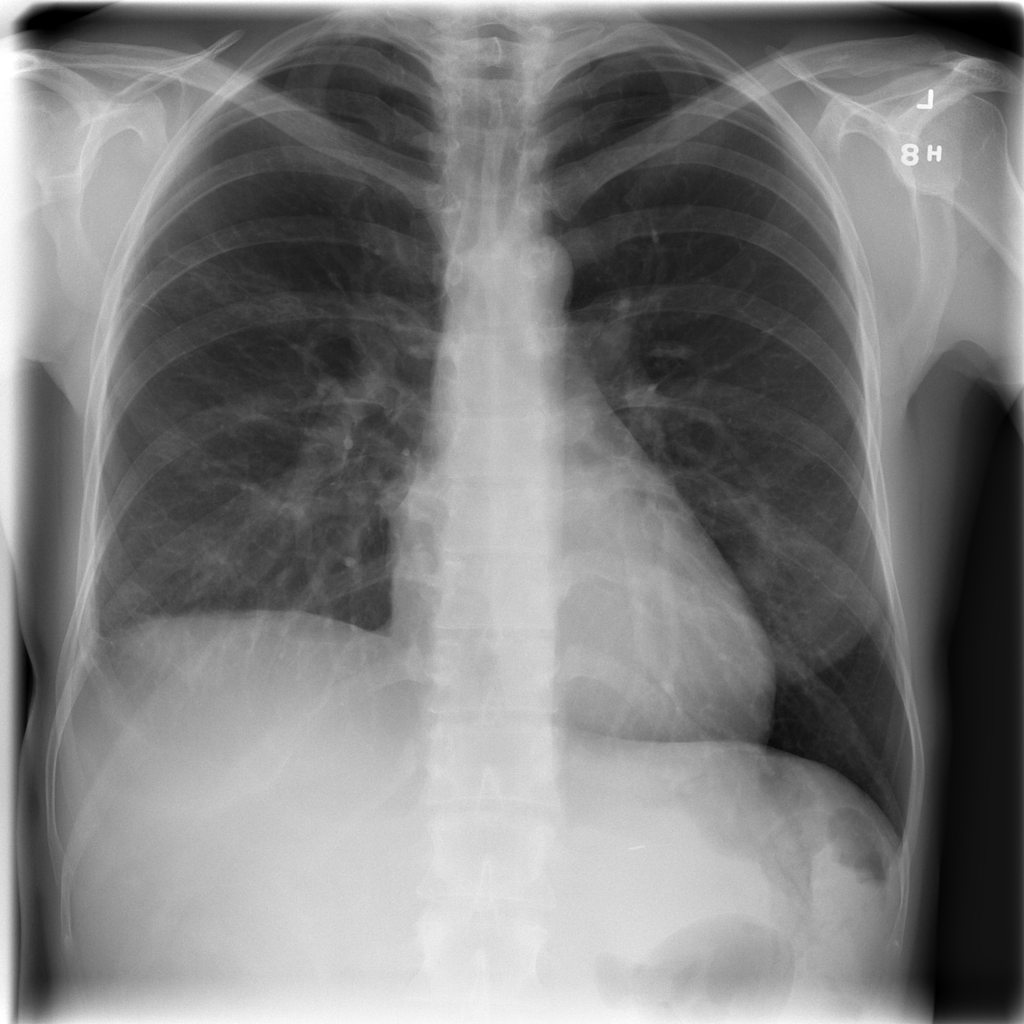

PAT-E066 · IMG-010Fibrosis

PAT-E066 · IMG-010

PA